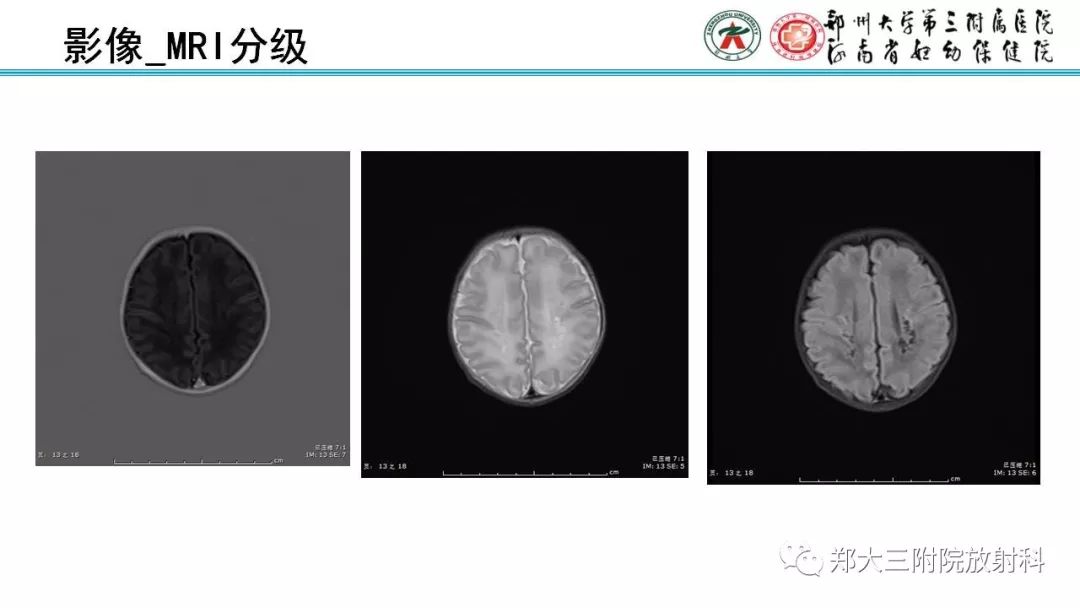

PVL脑室周围白质软化症的影像表现

【PPT】PVL脑室周围白质软化症的影像表现